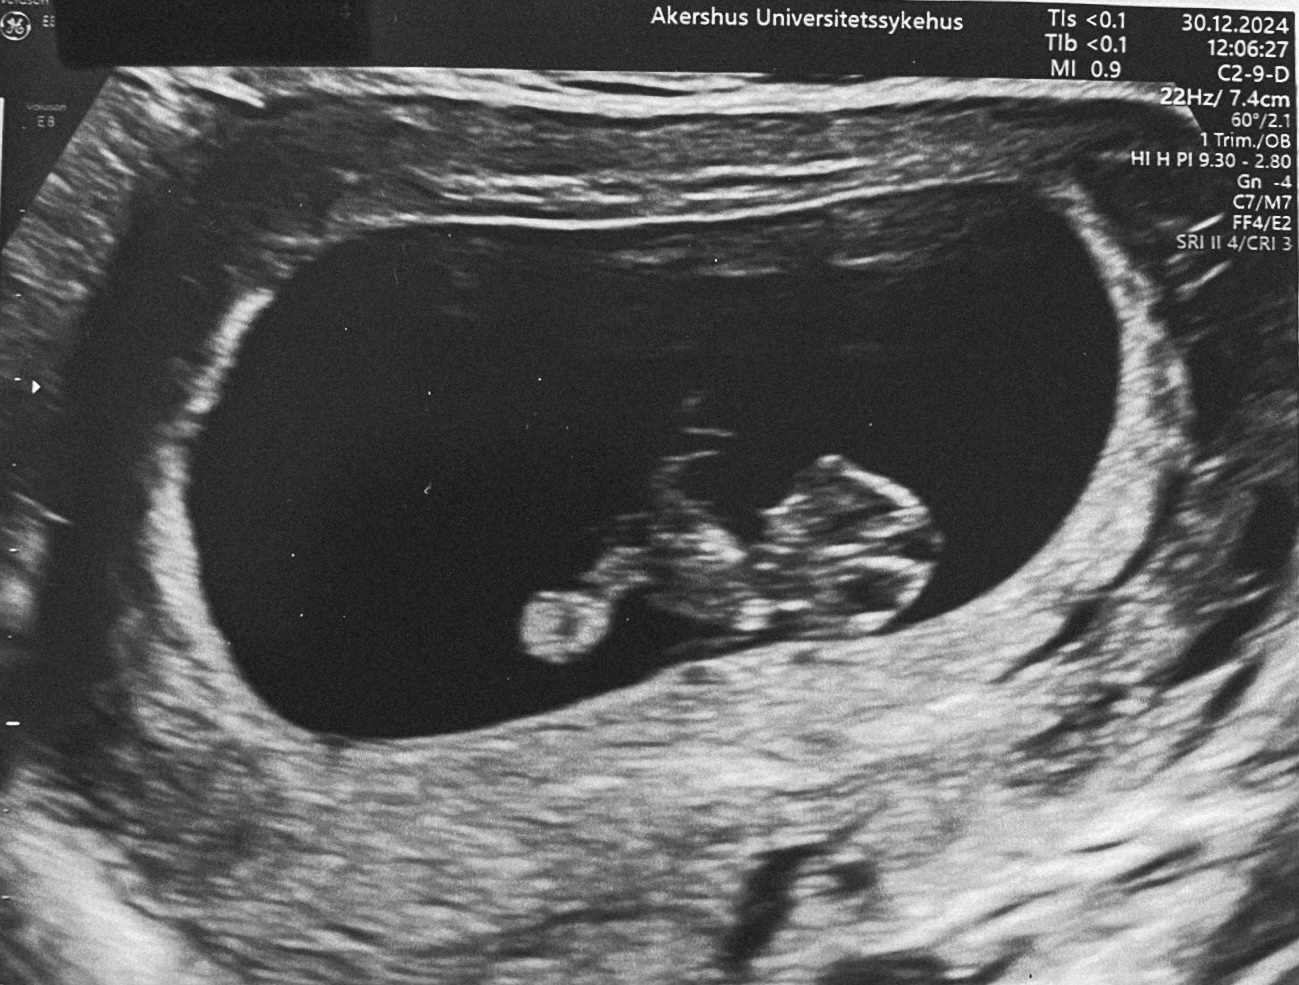

Søvnen er fortsatt krisedårlig og det føles egentlig bare som at den blir verre. Med oppvåkninger etter hver eneste søvnsyklus samtidig som at V sliter med å finne søvnen er grobunn for mye frustrasjon både hos oss og hos V. Nettene er preget av mye gråt og uro. Vi tror også V er en del sulten på nattestid for det nattammes fortsatt men jeg har nok mistet en god del melk pga. graviditeten så vi har en teori om at V fortsatt driver og omstiller seg nå som melken er synkende samtidig som energibehovet øker pga. flere faktorer. Flere ganger den siste tiden har vi måtte gi en klemmepose med grøt på nattestid og den har gått ned på høykant også har V lagt seg rett ned og sovnet etterpå så noe er det hvertfall men nøyaktig hva det er det er, det er det vanskelig å si. V har blitt merkbart tyngre den siste måneden så jeg er litt spent på neste vektkontroll. Nytt er også at V blir skikkelig hangry og at V har behov for større porsjoner med hyppigere intervaller. Det er ikke alltid jeg klarer å henge med for endringen har kommet brått på, men vi gjør så godt vi kan. Jeg har i større grad også begynt å la V drive på med BLW og det fungerer egentlig veldig bra også blir det mindre stress for oss begge to, samt at jeg kan spise samtidig for jeg må også spise ofte for å holde kvalmen noenlunde i sjakk.